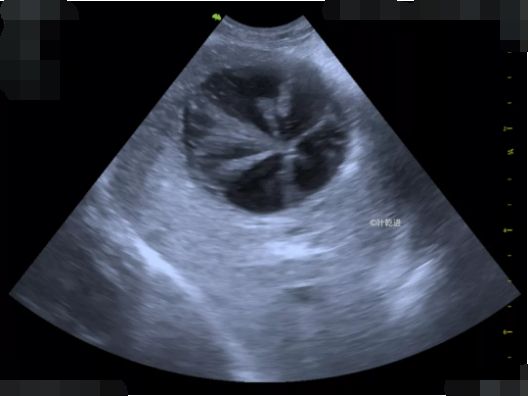

胆囊含有无回声胆汁且壁薄(猫约1 毫米;狗≤ 2mm)。在猫中,偶尔出现双叶胆囊是正常的。胆汁通常是无回声的,但不同程度回声的胆沙可能是悬浮颗粒或沉淀性的内容物在胆囊中积聚。产回声性内容物有时可能是偶然的,并不一定与胆道疾病有关。如果胆囊分泌过多的胆汁和粘液并肿胀或膨胀,就会发生胆囊粘液囊肿。胆汁受阻,无法正常流动并发挥作用

胆囊扩张且伴有低回声粘液积聚的可归类为胆囊粘液囊肿,但也可归类为胆汁凝固、粘液性增生、囊性增生和其他相关病症。胆囊粘液囊肿在老年小型犬中更常见,在猫中很少见。胆囊粘液囊肿的形成是一个连续的过程,从胆汁产回声开始,然后是星状图案,最后是猕猴桃征(即,低回声粘液的圆形堆积,含有细的星状高回声条纹)。粘液囊肿的确切病因目前仍存在争议。但其临床重要性很重要,因为它们可导致胆囊破裂、胆汁性腹膜炎。